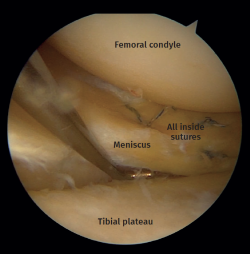

Meniscal tears were the most frequent soft tissue lesion (Figure 4), noted in 26 of the 40 patients evaluated (65.0%). The highest meniscal tear rate was seen in type II tibial plateau fractures (type I: 15.3%; type II: 80.7%; type III: 4%). Table 1 shows the number of meniscal injuries for each fracture type.

Figure 4. Left knee. View from the anterolateral portal. Peripheral longitudinal tear involving the lateral meniscus body.

Of the 15 lateral meniscus injuries, there were 9 radial tears treated with partial meniscectomy and 6 peripheral tears that were sutured with a combination of an outside-in and an all-inside technique (Figures 7 and 8).